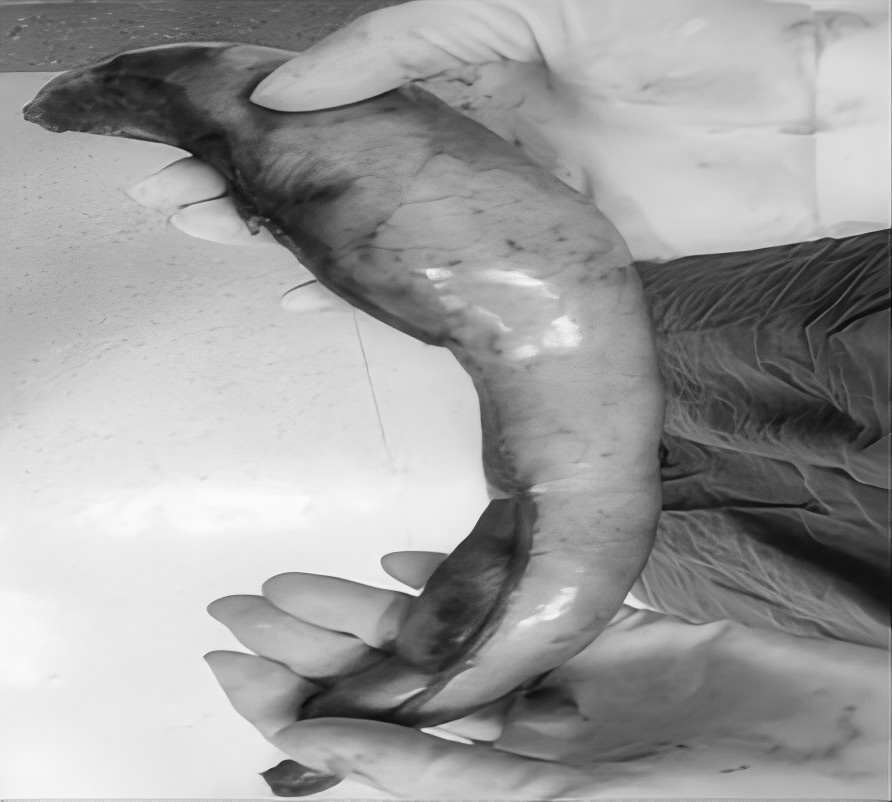

近日,贵州航天医院普外科特邀贵州医科大学附属医院胃肠外科严芝强博士前来我院开展“腹腔结核的综合治疗”学术讲座,严博士结合临床实际案例,带来了腹腔结核综合治疗的前沿知识和宝贵经验,深入浅出地讲解了腹腔结核的发病机制、诊断要点、最新治疗策略及药物精准治疗、把握手术干预时机、营养支持等关键环节,为提升我院腹腔结核诊治水平奠定了坚实基础。 今天,小编就带领大家回顾讲座内容,你想要了解“腹腔结核”知识都在这里! 什么是腹腔结核? 结核病是由结核分枝杆菌引起的传染病,曾是单一传染源死亡的主要原因,能影响身体多个器官,腹腔结核就是其中之一,包括胃肠道、腹膜、肠系膜淋巴结等部位的结核病。 腹腔结核常见症状 消化系统症状:常见为腹痛,可能伴有呕吐、腹胀、恶心、腹泻或便秘等症状。如:频繁呕吐,无法正常进食;长期受腹胀困扰,腹部隆起。 全身症状:发热、盗汗、体重减轻等。如:不明原因地体重下降,身体逐渐消瘦,夜间睡觉时大量出汗。 腹腔结核发病原因 消化道感染:食(饮)用带菌牛奶或被结核菌污染食物,进入消化道后,结核菌在肠道淋巴组织中形成病灶,并可能蔓延至肠系膜淋巴结、腹膜等部位。如,经常喝未经严格消毒的牛奶,增加感染风险。 血行播散:身体其他部位的结核菌,通过血液循环到达腹腔,侵犯腹腔内器官。如肺结核,当患者免疫力下降时,结核菌就可能“乘虚而入”进入血液,进而播散到腹腔。 淋巴结播散:胸腔内淋巴结结核或全身粟粒型结核,结核菌可通过淋巴管道传播至腹腔淋巴结,引发腹腔结核。 腹腔结核治疗方式 1.早期、联合、全程规范化抗结核治疗(治疗原则)。 2.加强支持治疗。 3.抗结核化学药物治疗:一般三联或四联。 4.放腹水,可同时腹腔内注射药物治疗。 5.手术治疗:仅限于完全性肠梗阻、肠瘘或并发肠穿孔者,当本病诊断有困难,与腹内肿瘤或某些急腹症不能鉴别时,可考虑剖腹探查。 腹腔结核饮食注意 腹腔结核患者饮食少量多餐,控制高脂、肥腻食物摄入,多吃清淡、易消化的食物,适量补充高蛋白等营养,多吃富含纤维素的新鲜蔬菜和水果,促进肠腔及腔腹部蠕动,禁食辛辣刺激性食物,忌烟酒。 腹腔结核预防建议 如果感染腹腔结核,一定要到正规医院做正规抗结核治疗,积极配合,树立战胜疾病的信心,就能战胜病魔,恢复健康。 近年来,腹腔结核发病率呈上升趋势,因其诊疗复杂、病情多变,常累及肠道、腹膜等多脏器,致患者腹痛、肠梗阻,严重影响生活质量,甚至危及生命。 对此,贵州航天医院普外科依托结核内科结核病诊疗经验,积极开展腹腔结核外科治疗工作,通过内外科联合,着力打造腹腔结核诊疗体系,为遵义地区腹腔结核患者提供更加优质、全面的诊疗服务。 咨询信息:贵州航天医院便民服务电话(请点击跳转咨询电话页面) 注:部分图片来源于网络,如有侵权,请联系删除。 贵州航天医院普外科专家团队 梁 跃 普外科主任 主任医师 临床擅长:对普外科各类肿瘤手术具有丰富的临床经验。 毕业于遵义医学院,遵义市医学会小儿外科学分会常务委员,遵义市肛肠协会理事,遵义市医学会核医学分会(第二届)委员会委员;荣获第三期“黔医人才计划”优秀学员称号;主持市级课题1项,完成省级课题1项,在国内各类刊物上发表论文10余篇。 钱科洪 普外科 副主任医师 临床擅长:从事普外科临床工作30余年,对各类普外科疾病的诊治、乳腺、甲状腺、胃十二指肠、结直肠等疾病及疑难杂症具有丰富的临床诊疗经验。 毕业于遵义医学院临床医疗系,2009年前往中山大学附属第一医院微创外科进修学习,在国内各专业期刊发表论文数篇。 贵州航天医院普外科简介 基本情况 贵州航天医院普外科成立于1968年,前身属于航天部O61基地3417医院外一科,1998年3417医院、3427医院合并后更名为普外科,下设胃肠外科、肛肠外科2个亚专业科室,拥有在全市较为先进的专科设备和技术,是中国疝病专科联盟单位,贵州医科大学附属医院胃肠外科专科联盟单位。开放床位40张,配备医护人员21人。 专科特色 普外科致力于胃肠及肛肠疾病的外科临床诊治及科研,以腹腔镜微创外科技术为本,形成以快速康复治疗胃肿瘤、结直肠肿瘤、小肠肿瘤、直肠脱垂、肥胖病、急腹症、各类疝、痔、瘘等专科特色,同时注重胃肠疾病尤其是结直肠恶性肿瘤的基础研究和临床转化研究,总体诊断和治疗水平在区域同级医院居于领先水平。 开展手术:腹腔镜下胃癌根治术,腹腔镜下袖状胃切除术,腹腔镜下胃肠道间质瘤切除术,腹腔镜下结、直肠癌根治术,胃癌、结直肠癌的精准治疗,腹腔镜下小儿疝气、成人疝修补术,腹腔镜下阑尾手术,内痔的硬化注射治疗及痔疮的微创治疗:ATH、PPH、TST,直肠脱垂的各种手术治疗,难治性伤口VSD技术,鼻胃肠管、肠梗阻导管置入术,肛肠术后间歇性导尿技术,并引进了中医适宜技术,也为各种化疗患者提供输液港安装,提高患者就医体验。 腹腔镜下腹股沟疝无张力修补术 腹腔镜下腹股沟疝 无张力修补术 腹股沟疝里金斯坦(Lichtenstein)手术 PPH微创术治疗环状混合痔 黏连性或炎性肠梗阻-肠梗阻导管 腹腔镜袖状胃切除 腹腔镜阑尾切除术 腹腔镜阑尾肿瘤切除术 腹腔镜下结肠癌根治术 诊疗范围 胃肿瘤、结直肠肿瘤、小肠肿瘤、肥胖症、各类急腹症、腹部外伤、腹壁疝、便秘、直肠脱垂、痔疮、肛瘘、肛裂等胃肠、肛肠外科疾病。 END